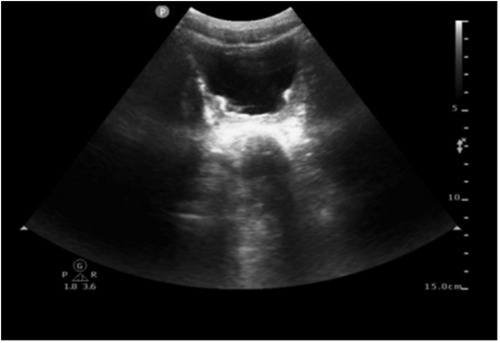

On day 23, the fluid balance assessment revealed a mismatch between the input of 2,476 ml and the output of 1,580 ml. Despite negative fluid balance, renal function tests (RFT) showed normal serum creatinine (29 μmol/L), ruling out acute kidney injury and directing focus to localized bladder pathology. The routine blood test showed an absolute eosinophil count of 30 cells/μl, which is within the normal range. Bladder ultrasound revealed inadequate bladder filling, bladder wall thickening (up to 6 mm), and a 22 × 7 mm hyperechoic mass suggestive of a calculus. On day 25, bedside EEG indicated a reduction in epileptic discharges, suggesting a further reduction of esketamine, midazolam, levetiracetam, and oxcarbazepine doses. Urinalysis revealed pyuria and microscopic hematuria. By day 27, the patient presented with mild erythema at the urethral meatus, and small red blood clots measuring 0.2 × 0.2 cm were observed in the diaper, indicating hematuria. A repeat ultrasound revealed insufficient bladder filling and an irregular thickening of the posterior bladder wall measuring up to 10 mm, as illustrated in Figure 1. The onset of hematuria and cystitis following 16 days of continuous high-dose intravenous esketamine infusion suggested a diagnosis of hemorrhagic cystitis, possibly due to esketamine. Based on the current literature and post-marketing surveillance data, midazolam, levetiracetam, and oxcarbazepine are not associated with hemorrhagic or inflammatory cystitis. According to the Naranjo adverse drug reaction probability scale in Table 2, the cystitis was classified as possibly related to esketamine use, with a score of 4 (6). Management included urine alkalization using a sodium bicarbonate dose of 40 ml, administered once daily for 12 days. By day 40, both urinalysis and urine sediment examinations had returned to normal. A summary of the urinalysis results during treatment is provided in Table 3.

Figure 1. Ultrasound image of bilateral kidneys/ureters/bladder. Ultrasound revealed insufficient bladder filling and an irregular thickening of the posterior bladder wall measuring up to 10 mm.